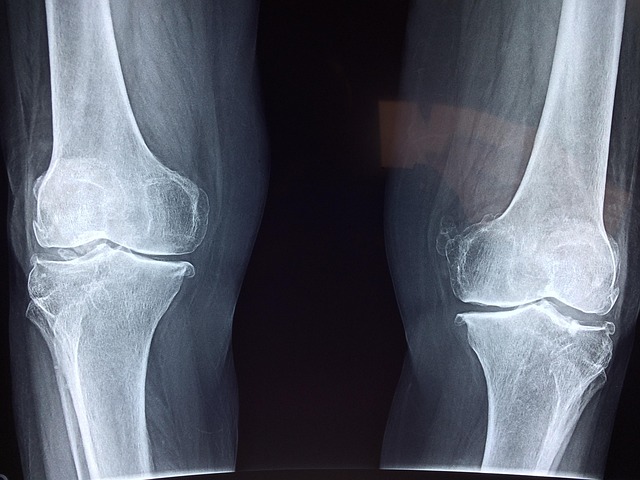

2) 영상 검사

- X-ray: 관절 손상 여부를 확인합니다.

- 초음파 및 MRI: 초기 염증과 관절 변화를 정밀하게 분석합니다.